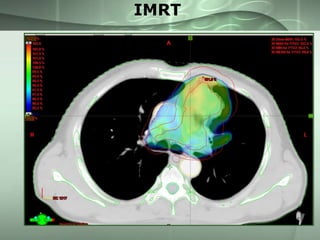

Advanced techniques

• Recent innovations

– 3 DCRT

– IMRT

– IGRT

IMRT